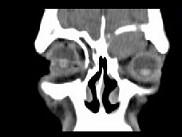

问题 男,53岁,近两年来渐进性头痛,伴左眼球外突,并向前下方移位,CT检查如图,最可能诊断为 ( )

选项 A、眶内炎性假瘤 B、眼格氏病 C、左额窦癌 D、左额窦黏液囊肿 E、额窦炎症

答案 D